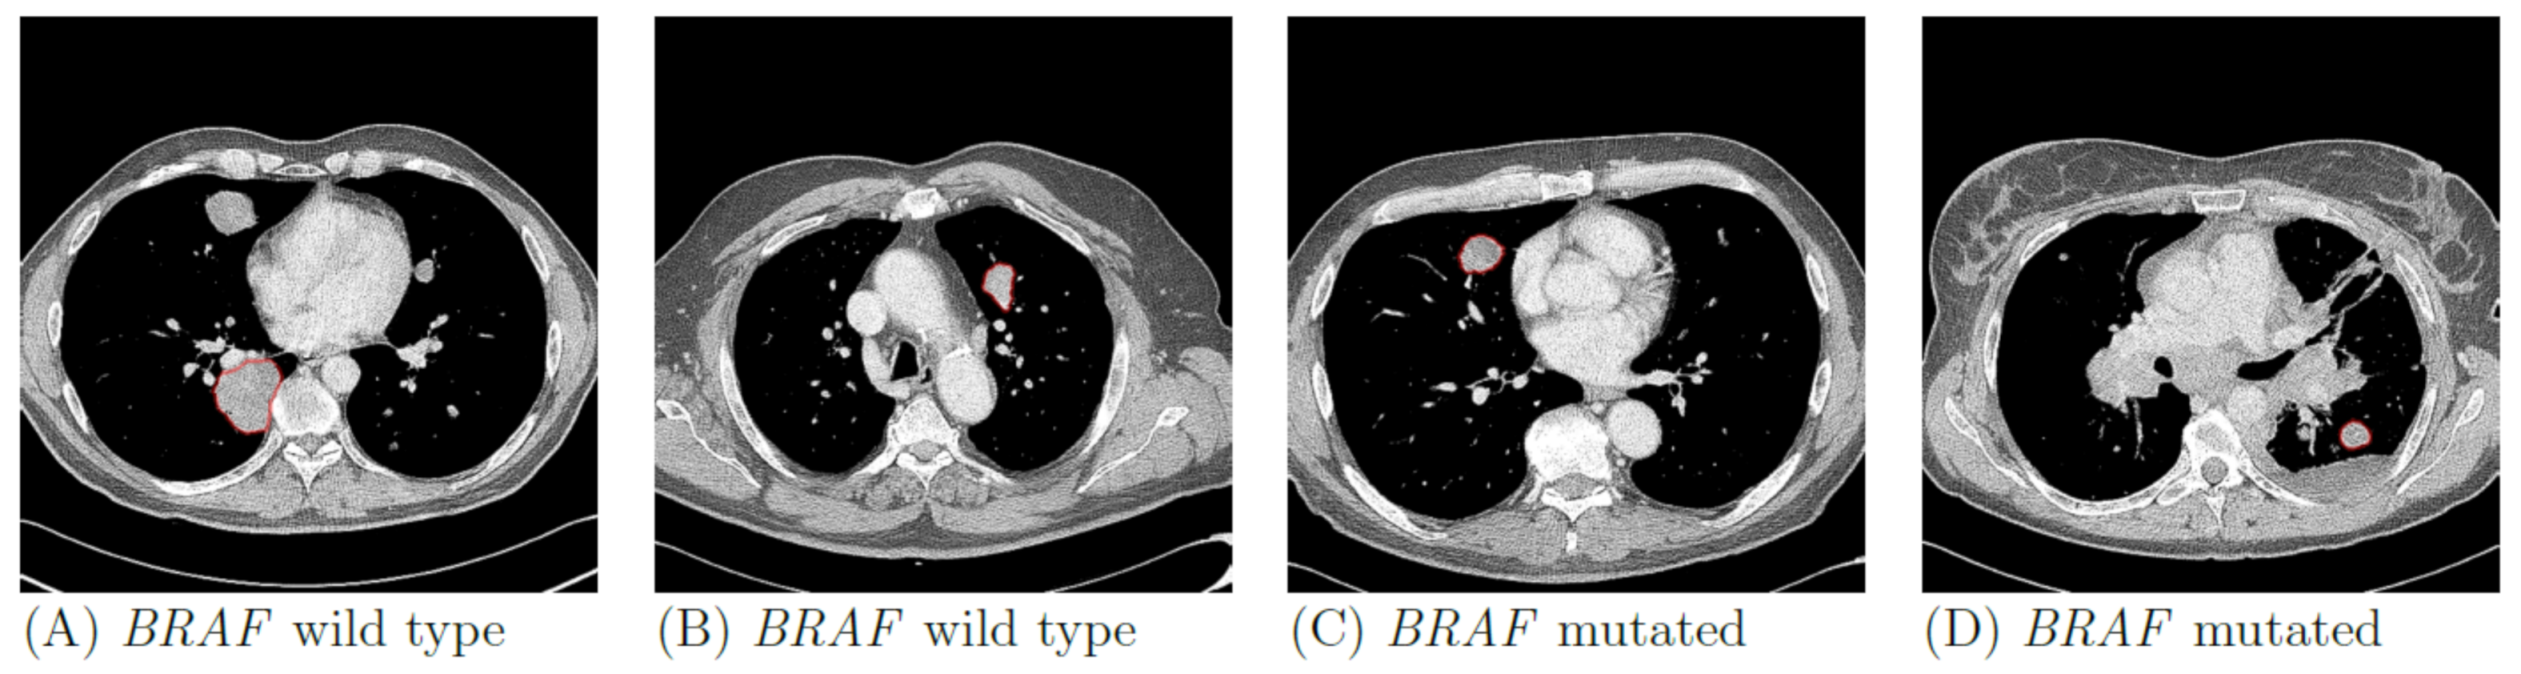

In total, 169 lung metastases in 103 patients were segmented. Figure 2 illustrates randomly selected segmentations of lung metastases from patients with BRAF-mt and BRAF-wt metastatic melanoma. Median volume of segmented lung lesions was 18.3 mL (IQR: 7.3–48.6 mL). None of the radiomics or LIDC features were significantly different between BRAF-mt and BRAF-wt lung metastases, as none of the features had a p-value < 0.05 after Bonferroni correction. LIDC criteria scores are shown in Table S2. Using all 169 lung metastases, the radiomics model (model 1) resulted in a mean AUC of 0.49, sensitivity of 0.61 and specificity of 0.37 (Figure 3A, Table 2). Model 2, i.e., only inclusion of the largest lesion per patient, slightly improved the performance (AUC of 0.65), whereas model 3, i.e., only inclusion of BRAF-wt melanoma who were also NRAS wild type, still had a poor performance (AUC of 0.49) (Figure 3B,C, Table 2). In addition, model 4, i.e., based on the LIDC features scored by a radiologist, resulted in an AUC of 0.46 (Figure 3D). The simple benchmark (model 5) resulted in a similar performance (AUC of 0.50).

Figure 2. Examples of BRAF wild type (A,B) and BRAF mutant (C,D) lung metastases of four patients with metastatic melanoma. Contours of the segmentations of the selected metastases are shown in red.